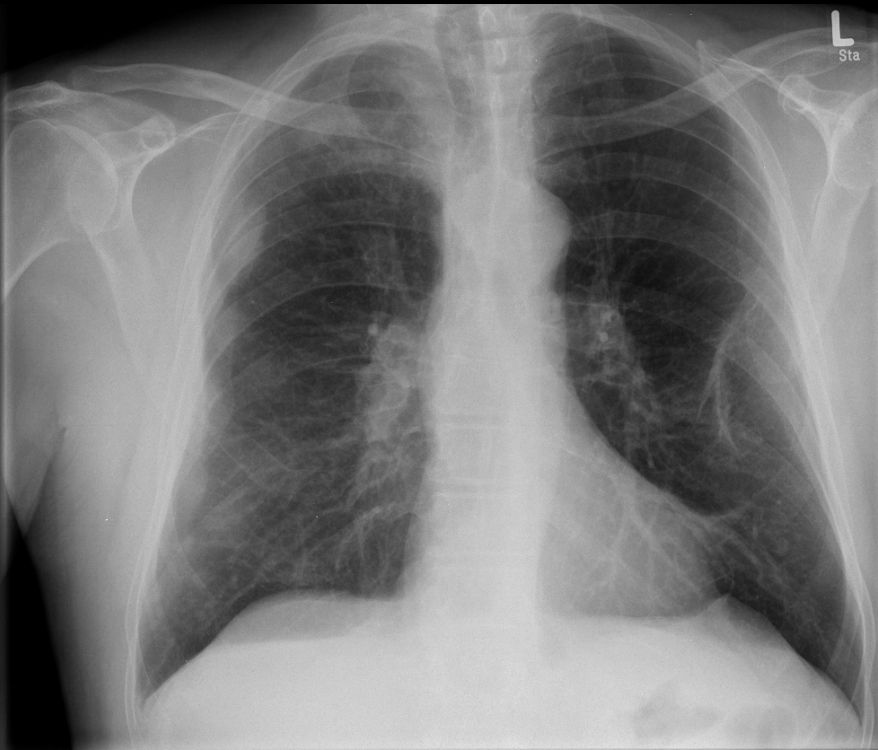

Röntgen Thorax Primärtumor im rechten unteren Unterlappen T2N3Mo. Nur diskrete Verdichtung im rechten unteren Hilus.